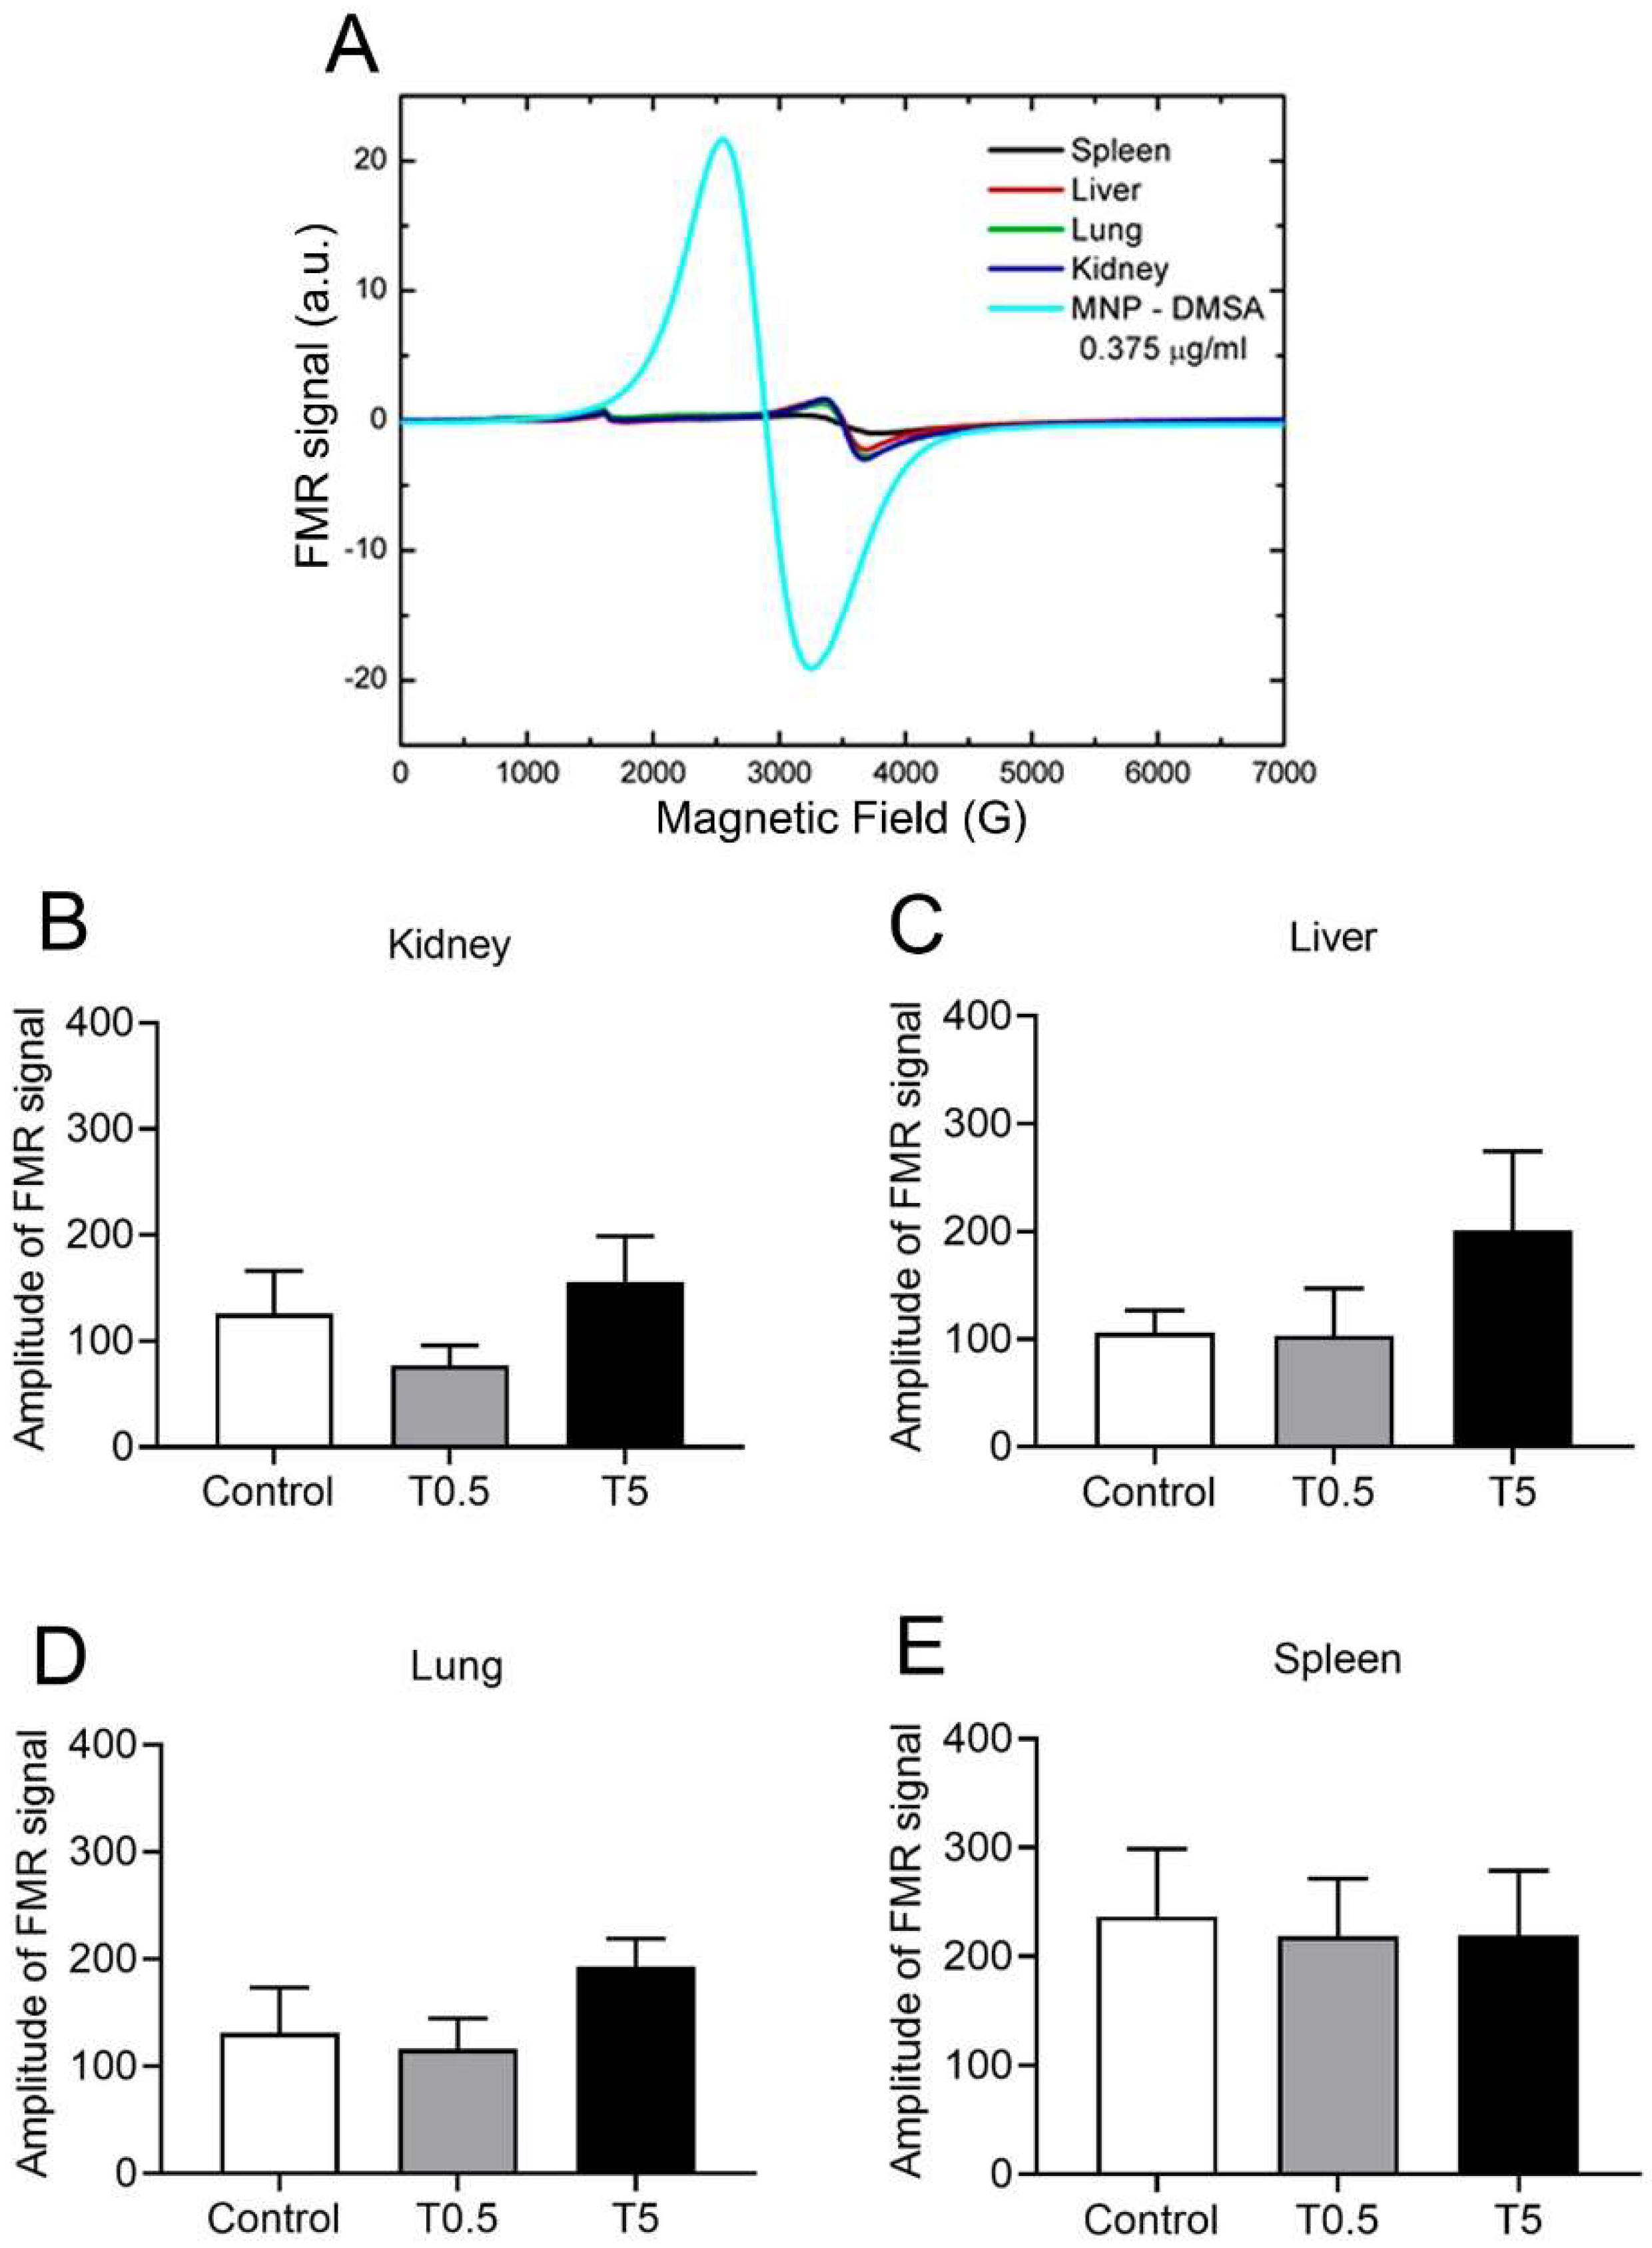

2.6. DMSA-MNP Detection and Quantification in Organs by Ferromagnetic Resonance (FMR)

3.5. DMSA-MNP Detection in the Organs